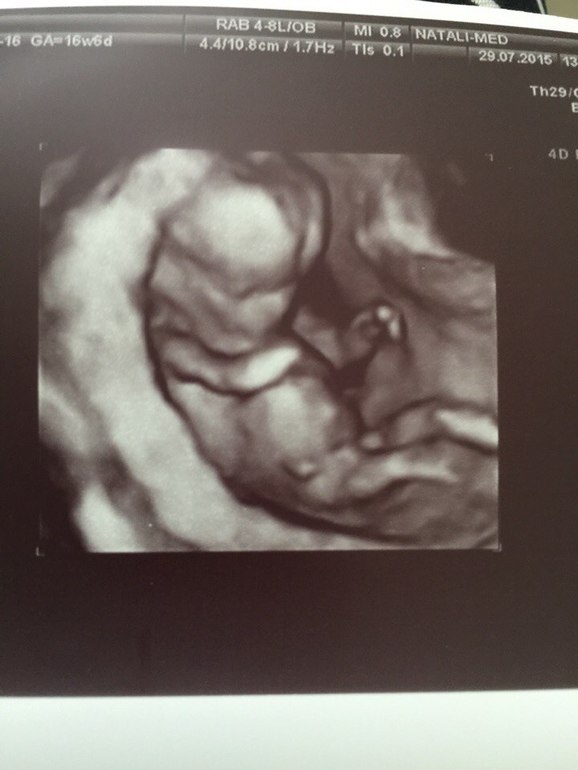

Малявочка моя показывала свой характер))) Упертый партизан. Отвернулся и начал пинать, руками прикрыл лицо, периодически почесывая живот. Нет у нас ни тонуса (кстати, за всю беременность, ТТТ, не было ничего). Плацента поднялась аж на 32 мм от зева и уже по задней стенке.

Малыш хороший, всем врачам он нравиться. Все на месте, выкрутасничает. Так же отметили, что у нас очень хорошая ровная спиночка, носик кнопка, ТВП просто заглядение, БПР вообще отличное, мозг просто зашибенный. Так же сказала, мол качек растет: бицуха у нас как у папки - сама видела на экране. В общем, к мелкому нет нареканий как и к остальному.ЧСС 150, КТР 80. - за неделю аж на 10 мм вымахали.

В общем, ребенок просто заглядение. Жду, когда можно будет уже разглядеть кто там сидит. Обожаю малявку.

Какой хорошенький))) Судя по 2 фото с узи там точно ярко выраженный парень)))Растите большими и сильными!